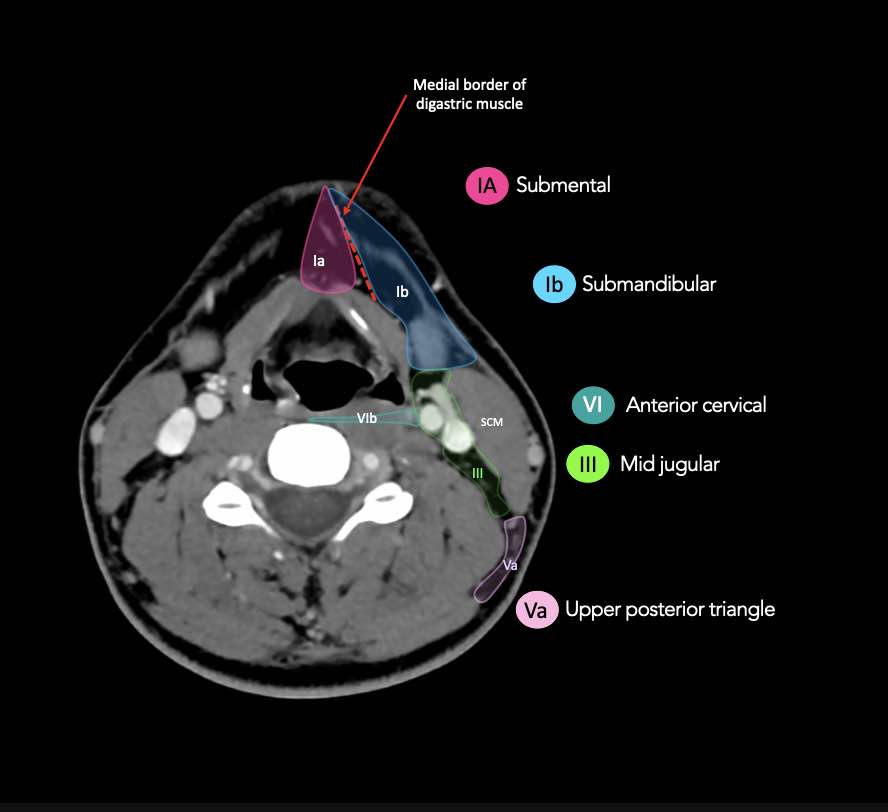

CT Scan Mặt Cắt Ngang (Axial CT)

Các lát cắt CT mặt phẳng ngang tương ứng với hình minh họa tổng quan.

Các lát cắt CT mặt phẳng ngang với hình ảnh chi tiết hơn.

Nhấp vào hình ảnh để phóng to.

I – Dưới cằm và dưới hàm

Các hạch bạch huyết ở tầng I có nguy cơ phát triển di căn từ các ung thư khoang miệng, hốc mũi trước, mô mềm vùng mặt giữa và tuyến dưới hàm.

Tầng Ia

là vùng giữa nằm giữa bụng trước của các cơ nhị thân, chứa các hạch dưới cằm.

Tầng Ib

chứa các hạch dưới hàm nằm trong khoang giữa mặt trong của xương hàm dưới ở phía ngoài và cơ nhị thân ở phía trong, từ khớp mu cằm ở phía trước đến tuyến dưới hàm ở phía sau.